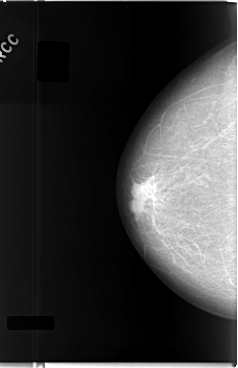

C_0027_1.RIGHT_CC

RIGHT_CC LINES 5888 PIXELS_PER_LINE 3808 BITS_PER_PIXEL 12 RESOLUTION 50 NON_OVERLAY